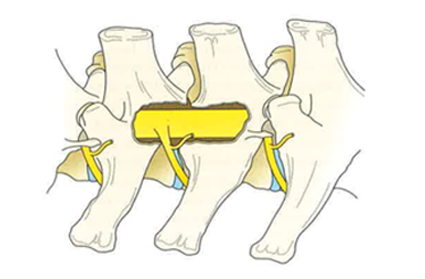

La neurologie étudie les affections au niveau du cerveau, de la moelle épinière, des nerfs périphériques et des muscles.

Un examen neurologique est également nécessaire avant un examen IRM. Un examen IRM prend du temps, il est donc essentiel de scanner la bonne région du corps de votre animal. Un examen neurologique préalable permet de définir la région à scanner. Il nous permet également d'évaluer la gravité des anomalies IRM que nous détectons au scanner.